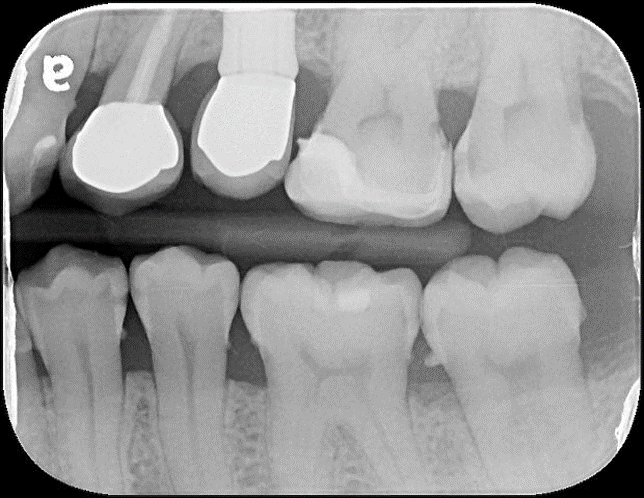

根尖照,邊緣完整

術前、術後比較